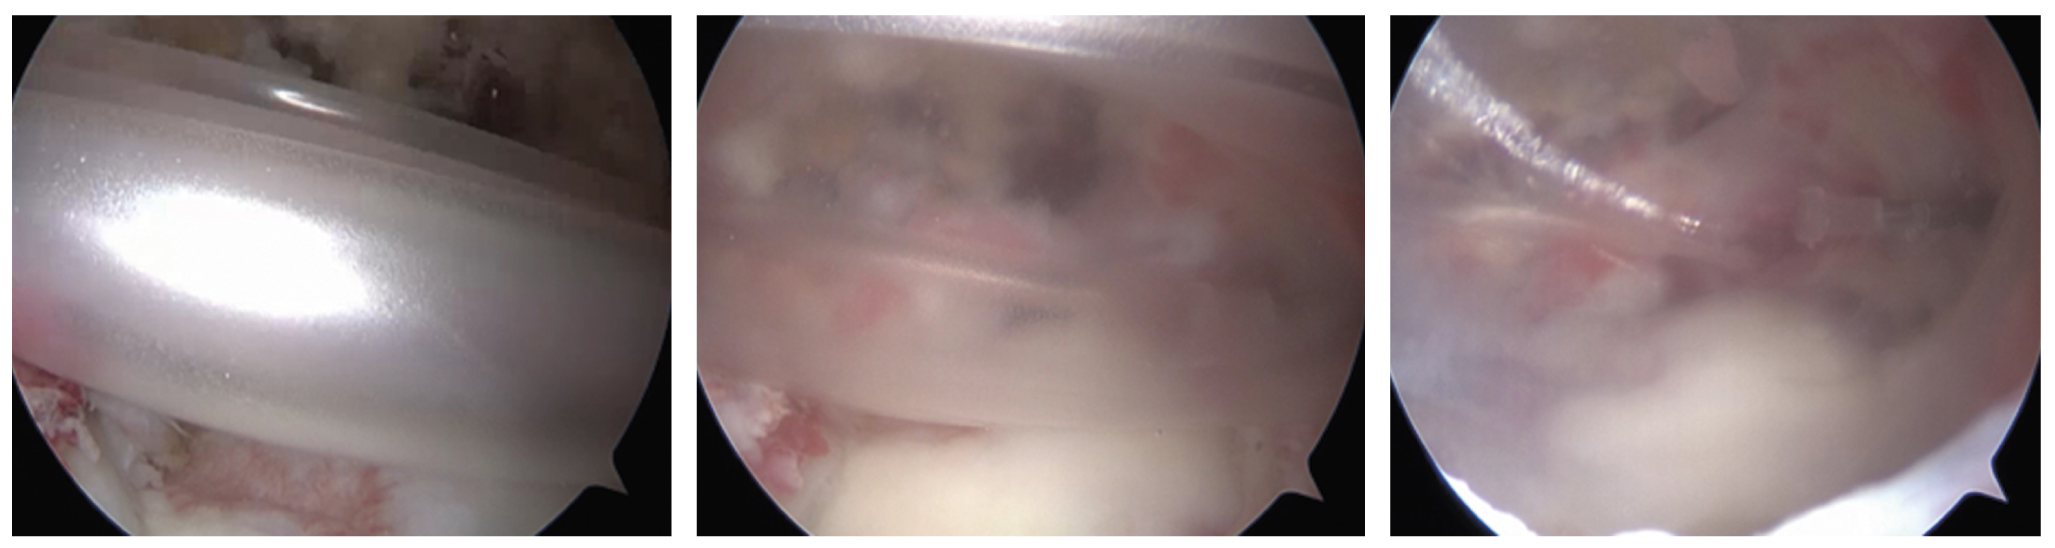

На контрольном осмотре через 6 мес все пациенты отмечали значительное уменьшение болевого синдрома в области плечевого сустава, восстановление его функции. Клинически отмечалось увеличение амплитуды движений в плечевом суставе, увеличение объема дельтовидной мышцы, восстановление чувствительности в дельтовидной области (табл. 2; рис. 8). Интенсивность болевого синдрома по шкале ВАШ составила 1±0,4 см (p <0,05), функция плечевого сустава по шкале DASH — 12±5,2 балла (p <0,05); сила дельтовидной мышцы по шкале BMRC (M0–M5) увеличилась до 4,6±0,48 балла (p <0,05). Амплитуда движений в плечевом суставе также увеличилась: сгибание 154±25,6°, отведение 156±22,4°, наружная ротация 50±8° (p <0,05). Толщина среднего пучка дельтовидной мышцы по данным УЗИ увеличилась до 10,6±1,12 мм (p <0,05). При стимуляционной электронейромиографии отмечалась положительная динамика в виде нарастания амплитуды М-ответа.

Рис. 8. Восстановление объема и контура дельтовидной мышцы после операции: a — вид до операции; б — через 6 мес после операции. / Fig. 8. Restoration of volume and contour of a deltoid muscle after the surgery: a — before the surgery; б — 6 months after the surgery.